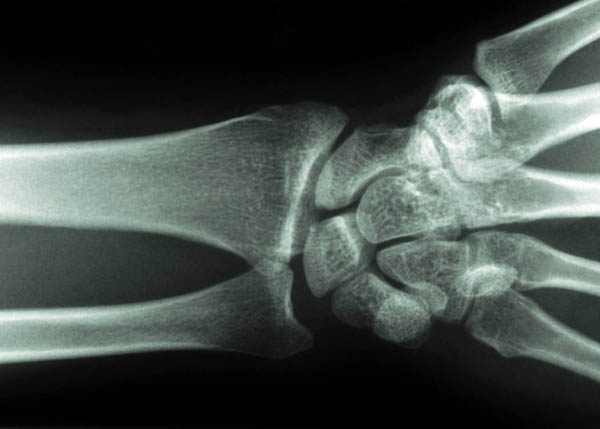

Wrist and Hand Pain

Some causes of wrist and hand pain are similar to those of the elbow pain; Overuse (Repetitive Strain injury – for e.g. inflammation of the tendon which attaches to the thumb, known as DeQuerins Tenosynovitis), referred pain, wear and tear, and carpal tunnel syndrome.

Repetitive Strain injuries – wrist is the most common area for these injuries. They result in stiffening of the joints as well as inflammation of the wrist joints and some tendons.

Wear and tear – This is usually more common in the wrist and the hand than in the elbow despite the fact that all the joints are non – weight bearing. This is because the hand and wrist are used all the time, with everything we do and the weight of objects we may carry strain the wrist and hand joints.

Hands and Wrists are commonly affected by Osteoarthritis and Rheumatoid Arthritis.